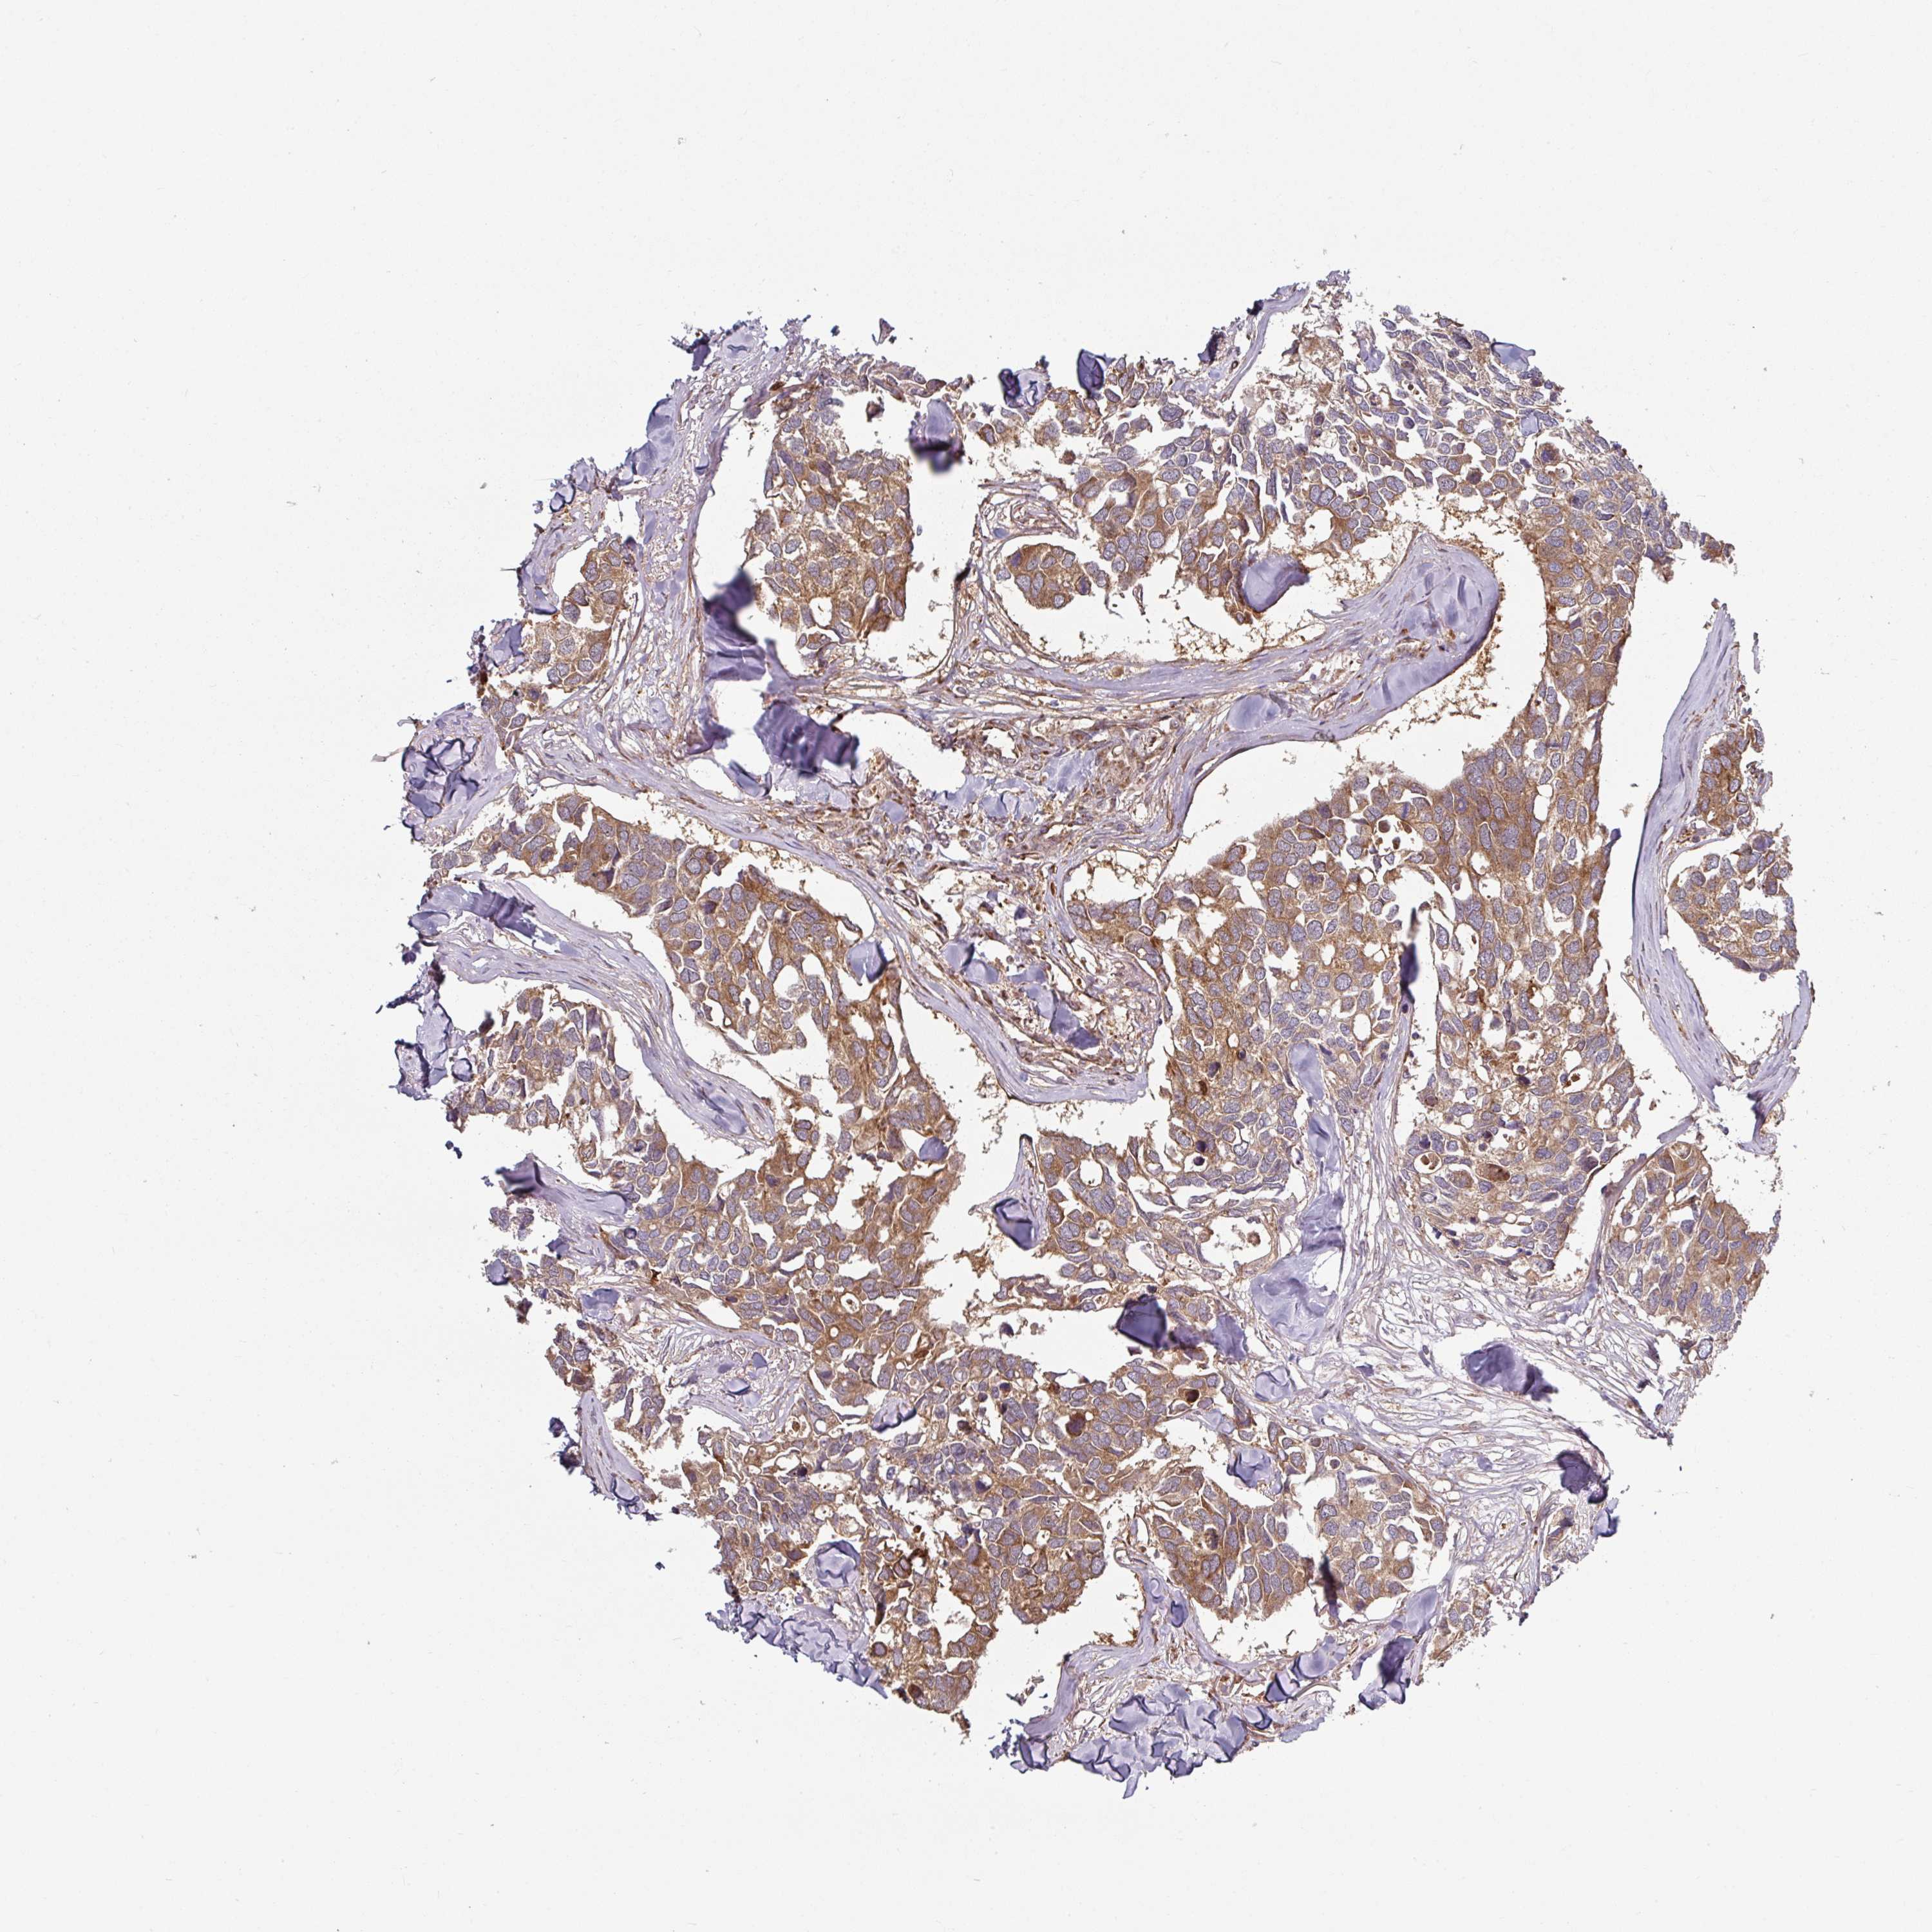

CANCER BREAST CANCER Show tissue menu

BRCA TCGA BRCA VALIDATION PROTEIN EXPRESSION

ANTIBODIES

AND

VALIDATION